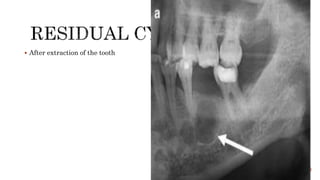

 Infection from carious tooth spreads to the pulp of the tooth

 Formation of granuloma and abscess

 Around the crown of the unerupted tooth

 After extraction of the tooth

 Benign intraosseous tumours arising from the dental lamina.

 Like dentigerous cysts, OKCs are also often associated with unerupted or

impacted teeth. However, unlike dentigerous cysts, these cysts when large envelop

the entire tooth and not just the crown.

 Characteristic pattern of growth - expansion along the axis of the mandible with